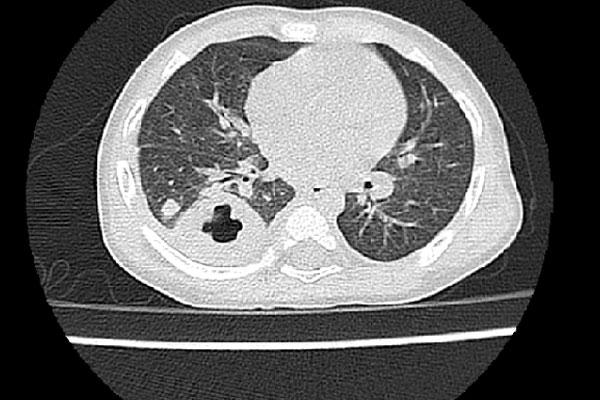

Một bệnh nhân tại MRC

Ảnh minh họa một người nhiễm mycetoma

Mycetoma gây ra bởi vi khuẩn hoặc nấm